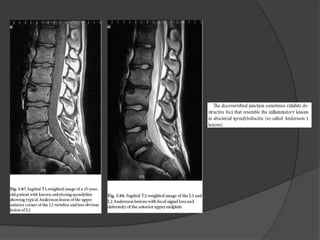

Exames de Imagem

 RNM.

RM